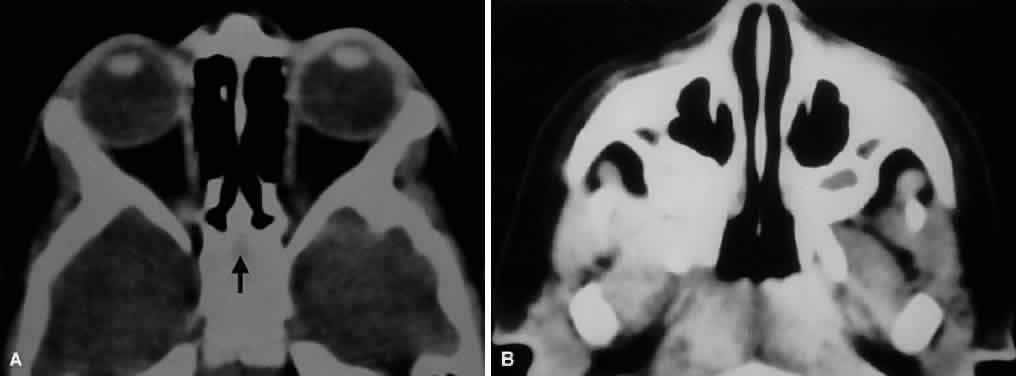

The ethmoidal sinuses can be observed to begin to take shape between the 6th and 8th weeks of gestation and are fully developed at birth. The remaining paranasal sinuses develop much later, with the sphenoid and frontal sinuses continuing to pneumatize into adolescence or early adulthood (Fig. 5). This accounts for the high incidence of orbital cellulitis from adjacent ethmoiditis in children. The lamina papyracea separating the orbit from the ethmoidal air cells is thin and perforate in children, providing easy access for microbial spread. Because the remainder of the sinuses are rudimentary in children, they are rarely the source of orbital infectious processes. Most of the orbital bones are formed during the 3rd month, although their ossification ensues over the next several months. At term, the orbit is nearly hemispheric, and the bony perimeters closely hug the globe.17

Fig. 5. Axial CT of paranasal sinus development in a 2-year-old child. A. Note that the ethmoid air cells are pneumatized, but the future sphenoid sinus is seen only as a faint lucency (arrow) within surrounding bone. B. Rudimentary maxillary sinuses have already partially pneumatized.

The orbit is surrounded on three sides by the paranasal sinuses (see Fig. 5). The ethmoid sinus runs along the medial orbital wall and is divided into anterior, middle, and posterior air cells by a highly variable system of septa. It is the only sinus to be fully pneumatized at birth. The thin lamina papyracea of the medial orbital wall and the vascular foramina for the anterior and posterior ethmoidal arteries provide scant resistance to the extension of infections and tumors from the ethmoidal sinus to the orbit, even in the adult (Fig. 10).